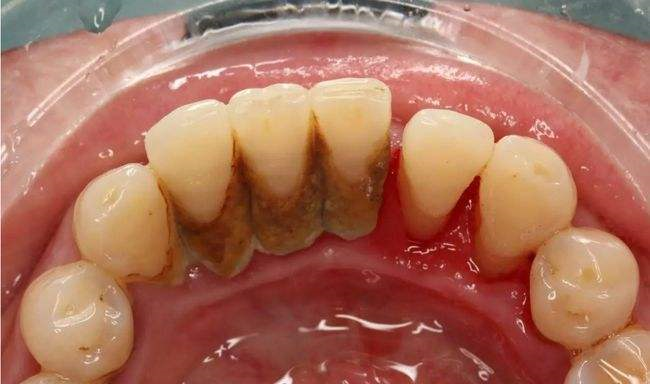

導(dǎo)致牙齦炎最主要的因素就是牙菌斑,而且只是在牙齦上不會(huì)那么快擴(kuò)散開來的,所以如果想除去牙菌斑,首先就是要得到有效的良好的治療,比如不是那么嚴(yán)重的,通常采用洗牙清除牙結(jié)石,是可以控制住菌斑的,假如是遇到了牙齦增生,那么就必須要切除部分的牙齦,這樣來恢復(fù)牙齦的生理外形,在通過有效的治療后,盡管牙齦炎和牙齦形態(tài)都恢復(fù)正常以后,為了有效的保持鞏固,刷牙時(shí)每天必須要堅(jiān)持的,務(wù)必要養(yǎng)成良好的口腔衛(wèi)生習(xí)慣,如果牙齦炎要是不治療的話,就任由他的病發(fā)繼續(xù)發(fā)展下去,那么細(xì)菌就會(huì)侵犯到深部以及牙周組織,慢慢的演變成了牙周炎。

其次還會(huì)有牙周袋的形成,如果是沒問題的情況下,比較健康的牙齦齦溝深度是不會(huì)超過2mm,如果是已經(jīng)超了兩毫米那么這就是牙周袋,牙周袋的形成,在這種情況下就足以說明牙齦炎已經(jīng)發(fā)展到了牙周組織上了,促使牙周組織的感染會(huì)深入,慢慢的膿性分泌物就會(huì)從牙周袋冒出來,牙周炎的主要癥狀之一就是牙齦萎縮,但是一般我們是察覺不到的,在長(zhǎng)時(shí)間的在大量牙石壓迫刺激牙齦下,就會(huì)產(chǎn)生齦緣外形出現(xiàn)水平式的退縮癥狀。